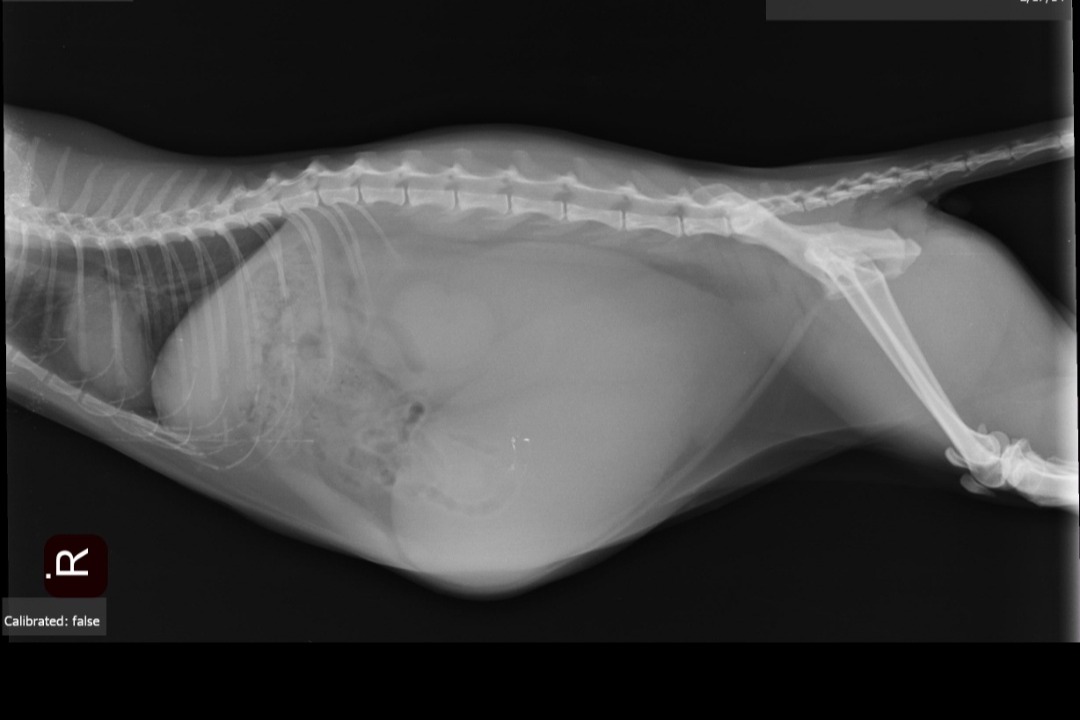

We recently took our cat to the vet to checkout a problem we noticed her have, turns out its serious and the vet suggests a $3000 surgery or euthanasia, both options are pricy and we dont even seem to have much of an option to keep the remains or ashes..

Kurama is 7 years old, originally the smallest out of litter from a street cat. We provided her a good life and spoiled her plenty but it really breaks my heart seeing things be the way they are..